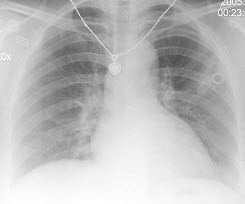

25、单项选择题

男,8岁,易疲劳,活动后心悸、气急,结合图像,最可能的诊断是()

A.房间隔缺损

B.室间隔缺损

C.肺动脉狭窄

D.动脉导管未闭

E.法洛氏四联症

点击查看答案